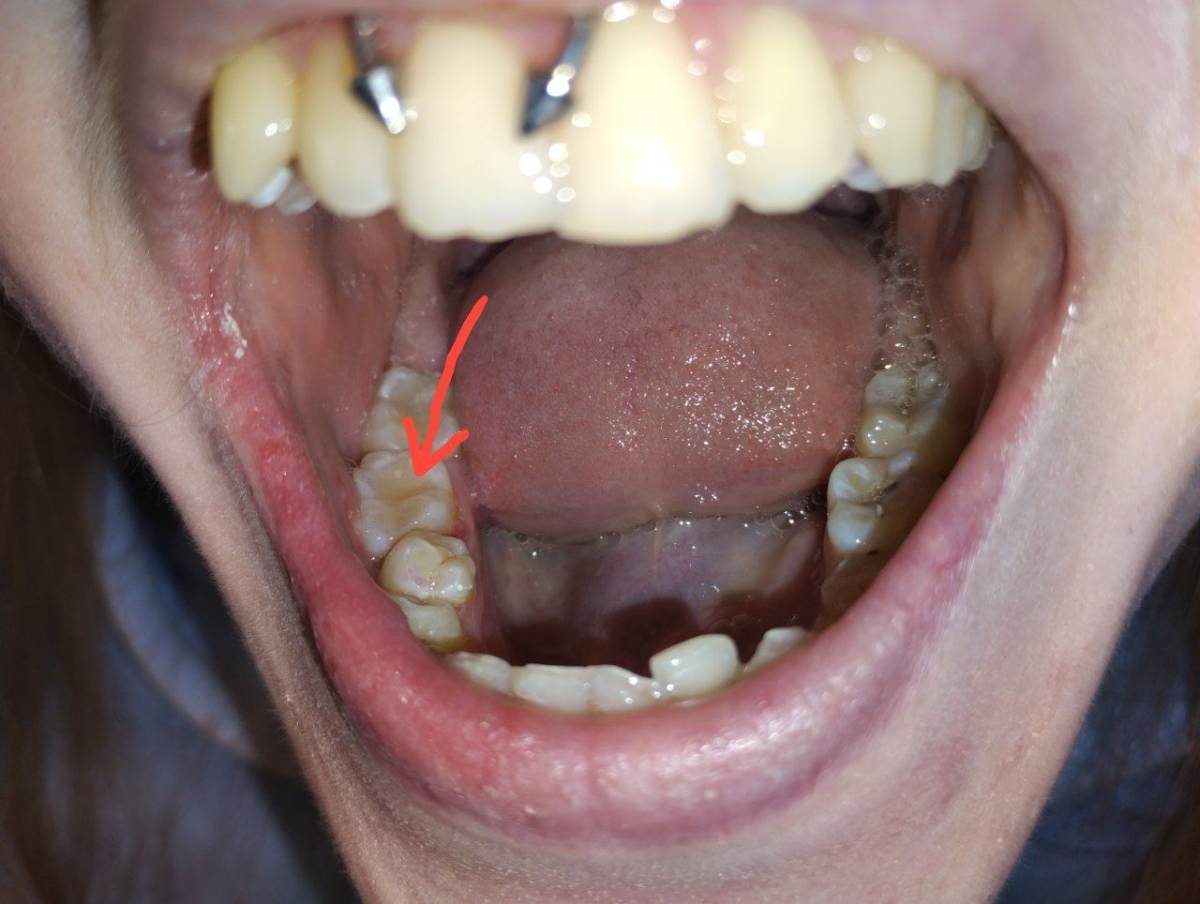

АнтонТЛТ Опубликовано 29 апреля Поделиться Опубликовано 29 апреля Отметьте, где болезненность Ссылка на комментарий

Александр1 Опубликовано 30 апреля Автор Поделиться Опубликовано 30 апреля В этой точке, пациент говорит в самом углу, боль ощущается при зондировании пломбы, сами ткани зуба безболезненны Ссылка на комментарий

red_butler Опубликовано 3 мая Поделиться Опубликовано 3 мая В 30.04.2026 в 06:07, Александр1 сказал: В этой точке, пациент говорит в самом углу, боль ощущается при зондировании пломбы, сами ткани зуба безболезненны скорее всего нарушение адгезивного протокола... Ссылка на комментарий

krokomot Опубликовано 5 мая Поделиться Опубликовано 5 мая В 30.04.2026 в 06:07, Александр1 сказал: В этой точке, пациент говорит в самом углу, боль ощущается при зондировании пломбы, сами ткани зуба безболезненны скорее всего вы мало отпрепарировали и ваш адгезивный протокол не выдерживает и происходит дебондинг, сформируйте классическую полость по блэку с отвесными стенками. Второй вопрос ваш протокол в студию, четко по секундам и мелочам, что за чем. протравил, просушил, нанес бонд не подходит, каждое дейстиве с секундах и повторяемость. Ссылка на комментарий